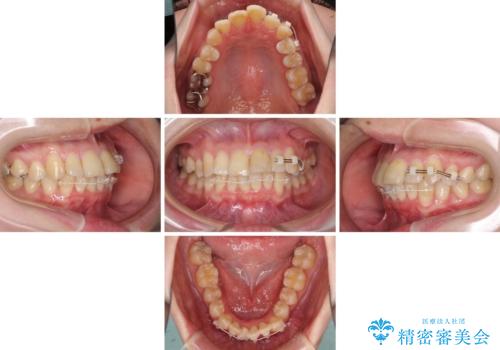

上下前歯のデコボコをきれいに インビザラインによる矯正治療

- インビザライン

- 2年4ヶ月

ワイヤー矯正を併用したことで前歯の叢生を速やかに解消することができました。

一方口元の突出感を改善するために時間がかかり、2年超を要しましたが、満足のいく仕上がりとなりました。